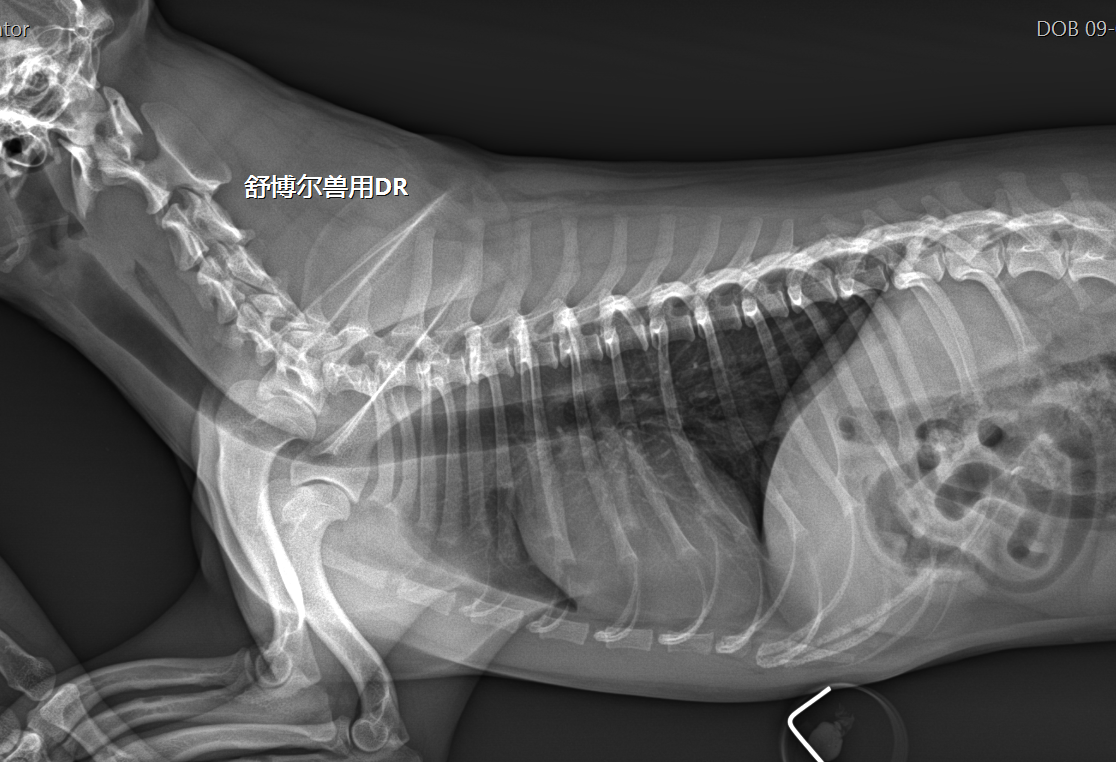

舒博尔公司创始人Dr. Chen在宠物数字化X射线成像设备相关领域具有十多年临床及产品研发经验,在该领域已经拥有十多项发明专利。 基于宠物X光拍摄的特殊性,X光拍摄过程中操作医生需要对宠物进行保定,医生长期处理暴露的X光辐射中,对医生健康造成极大伤害,所以如何减少医生的受照辐射是非常重要的研究课题,舒博尔产品研发重点考虑极大限度的保护医生眼晶体、甲状腺、乳腺、生殖性,舒博尔产品研发的宗旨是确保获取高清晰成像质量的同时,最大限度的降低宠医辐射剂量,为广大宠物医院提供既安全又好用的宠物DR。

深圳舒博尔宠物医学科技有限公司坐落于中国创新之城深圳,舒博尔公司创始人Dr. Chen在宠物数字化X射线成像设备相关领域具有十多年临床及产品研发经验,在该领域已经拥有十多项发明专利。 基于宠物X光拍摄的特殊性,X光拍摄过程中操作医生需要对宠物进行保定,医生长期处理暴露的X光辐射中,对医生健康造成极大伤害,所以如何减少医生的受照辐射是非常重要的研究课题,舒博尔产品研发重点考虑极大限度的保护医生眼晶体、甲状腺、乳腺、生殖性,舒博尔产品研发的宗旨是确保获取高清晰成像质量的同时,最大限度的降低宠医辐射剂量,为广大宠物医院提供既安全又好用的宠物DR。